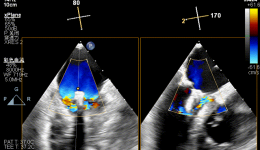

近日,宋先生(化姓)因心脏不适来我院进行超声心动图检查时,医生发现其室间隔上部存在连续性中断,三尖瓣隔瓣与室间隔缺损的右室面黏连,并在瓣尖部观察到5mm的缺损,缺损上缘距离主动脉右冠瓣仅2mm。未发现主动脉瓣脱垂和反流(见图一)。于是,...